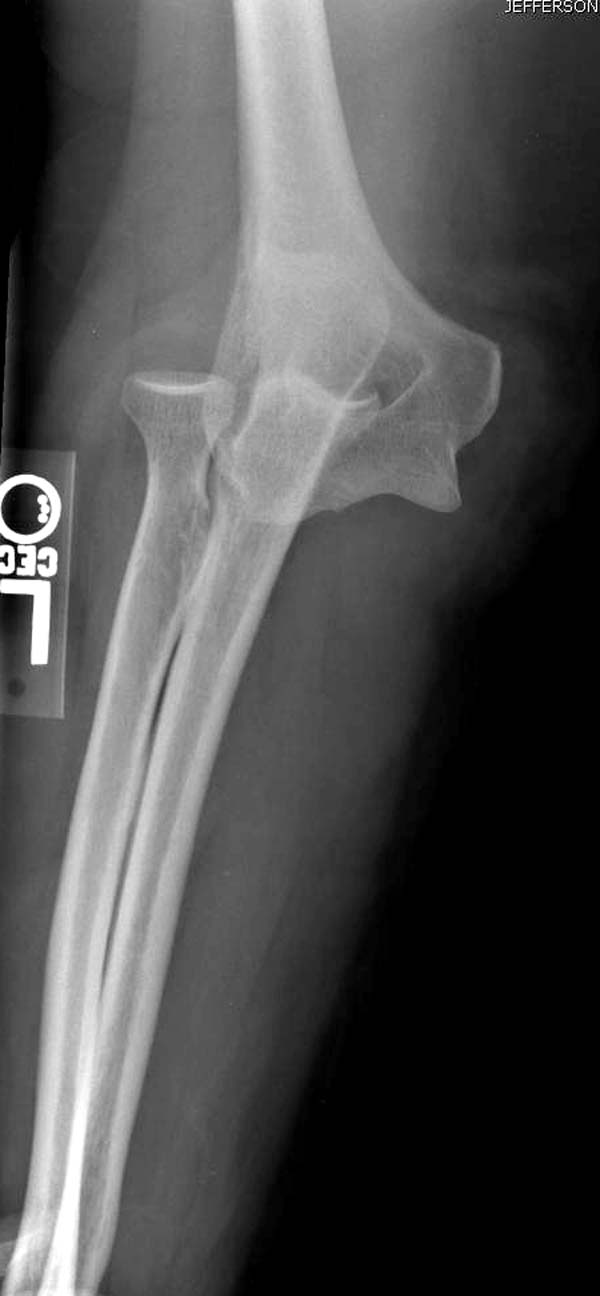

Снимки: 1-2 вывих, 4-5 вторичное смещение в гипсе, реконструкция

латеральной связки и капсулы 13-14, повторный вывих после реконструкции,

Вложение не в текстовом формате было извлечено…

Имя     : 5 Elbow dislocation postreduction.jpg

Тип     : image/jpeg

Размер  : 39536 байтов

Описание: отсутствует

Url     : http://weborto.net:8080/pipermail/ortho/attachments/20131212/4b05a6a3/attachment-0009.jpg